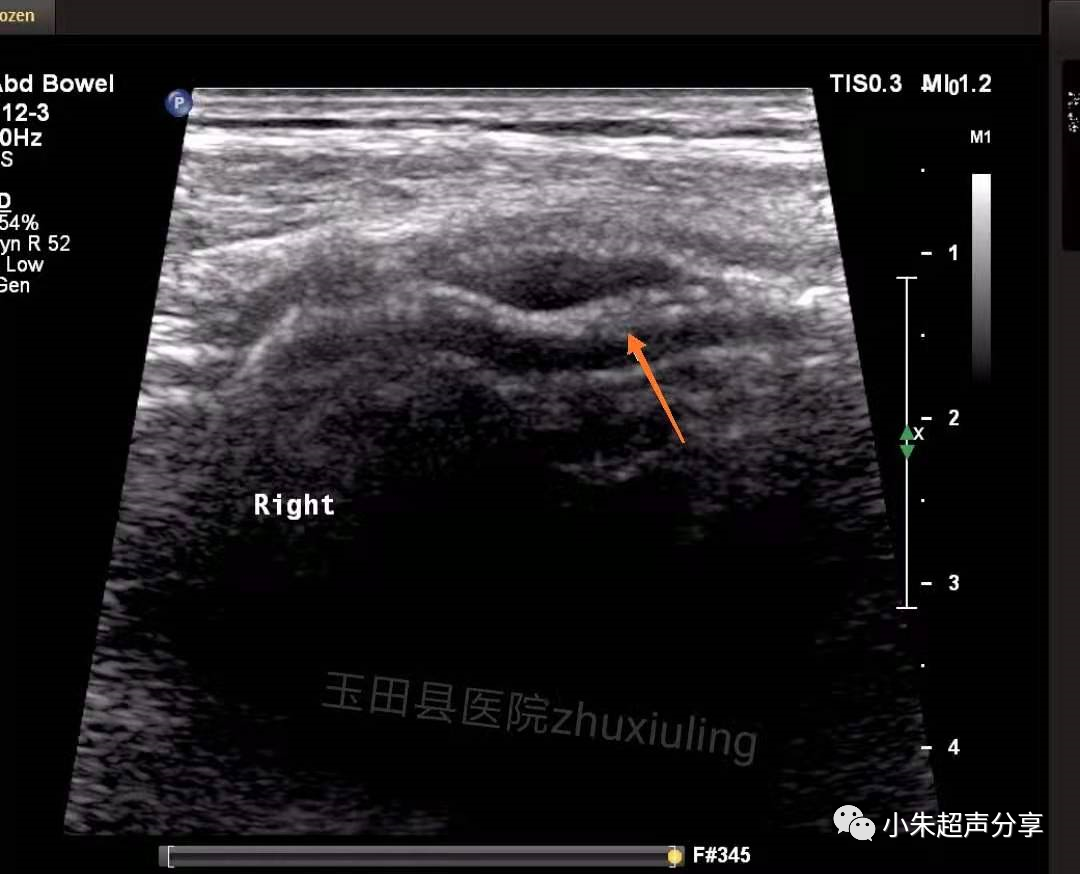

Case2:男,双侧腹股沟疝术后1月,双侧腹股沟区及阴囊疼痛,左侧为著。

血清肿常表现为边界不清、形态不规则、透声差的无回声区,持续时间长者积液内可见多发分隔,无血流信号。在其内部或周边常可见到补片结构,病程长者,补片可卷曲变形呈波浪状(如Case2)。发现时应及时与手术医生沟通,必要时需多次穿刺抽吸,并需定期复查。Case1患者经抽液2次后好转出院(第1次抽出50ml淡红色液体,隔日抽出45ml淡黄色液体)。Case2患者经门诊保守治疗后痊愈。

该2例患者积液发生的部位亦有所不同,Case1患者积液位于右下腹腹腔内并与腹股沟区相通(考虑积液位置为原疝囊内),可能残留狭小缝隙,但未见腹腔内容物疝出;Case2患者积液局限于腹股沟区腹壁软组织内,未见与腹腔相通。